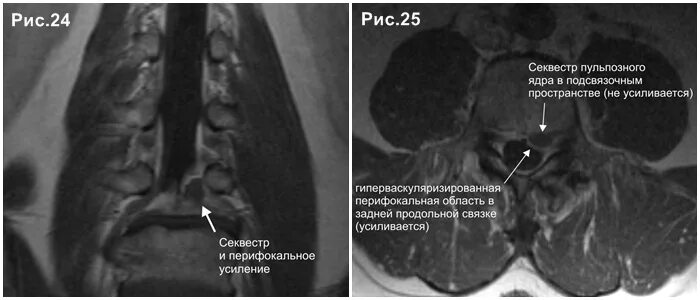

Каудальная миграция грыжи диска